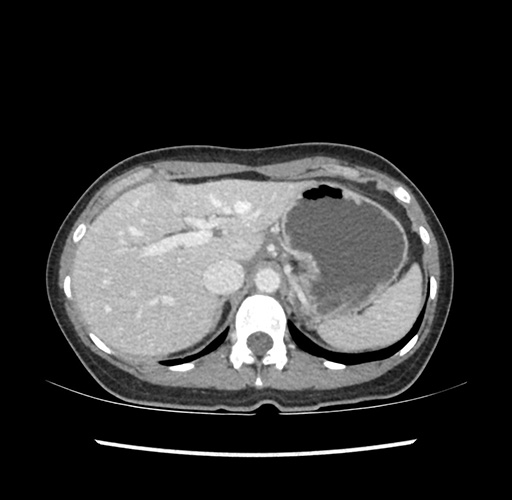

Imaging Analysis

Look through the patient's CT scan to identify any areas of concern for the necessary procedure.

Based on your CT findings, which issue(s) would give reason for "planned slowing down moment(s)" in this case?